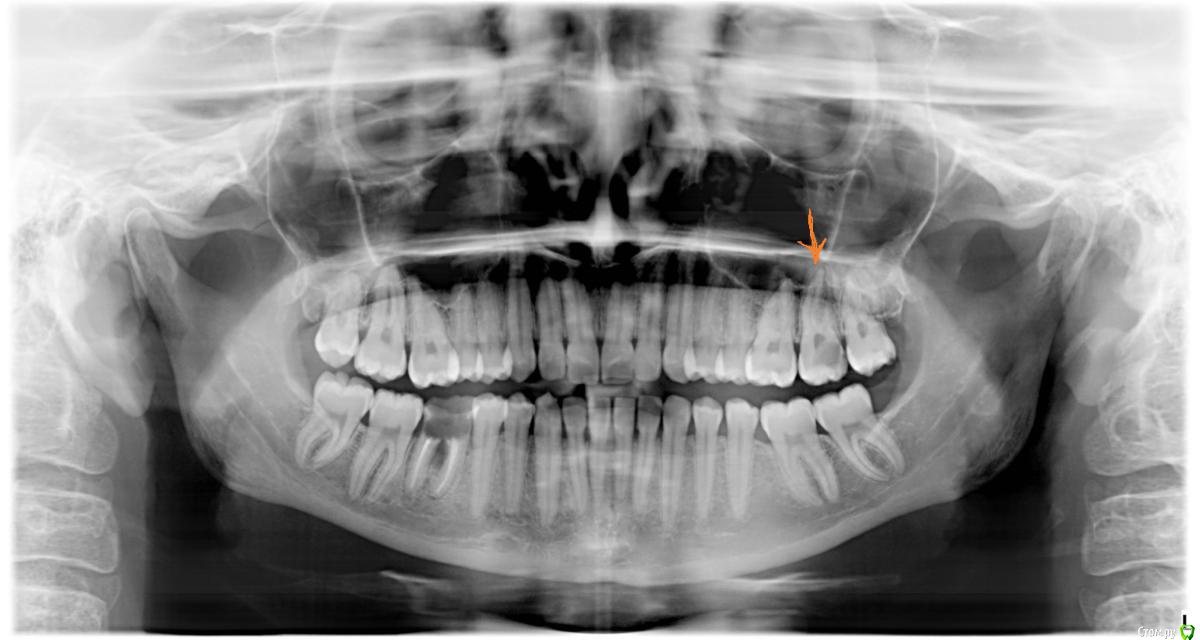

Оксана1318 Опубликовано 2 августа, 2017 Поделиться Опубликовано 2 августа, 2017 (изменено) Добрый день! Скажите, пожалуйста, сегодня я была на приеме у врача стоматолога. Она сделала снимок и сказала, что кариес глубокий, возможно даже пульпит. Пока точно она не видит, будет понятно только после того, как начнётся лечение. На фото это зуб шестерка справа . Со стороны оранжевой стрелки . На стрелку не обращайте внимания, этот зуб уже вылечили. Интересует шестерка рядом. Снимок сделан 7 месяцев назад. Скорее всего за это время стало хуже. Зуб не болел, все хорошо было вроде. Предлагали сегодня начать работу, но я не смогла по времени. Записалась на лечение через 4 дня. Скажите, может ли за эти 4 дня стать хуже? И если там нет пульпита, за эти 4 дня он может развиться? Очень переживаю, что не согласилась лечить сегодня. Новый снимок из клиники не забрала. Поэтому полугодовой давности только. Заранее спасибо! Изменено 2 августа, 2017 пользователем Оксана1318 Ссылка на комментарий

IvanK Опубликовано 3 августа, 2017 Поделиться Опубликовано 3 августа, 2017 Здравствуйте,так и не понятно, на что обращать внимание, какой зуб лечили?))) стрелка указывает на зуб, пульпит, возможно уже периодонтитрядом, 26, скорее всего кариес, если его Доктор видела во рту Скажите, может ли за эти 4 дня стать хуже? вряд ли И если там нет пульпита, за эти 4 дня он может развиться? вряд ли Не паникуйте. За 4 дня ничего не изменится Ждем новый снимок) Ссылка на комментарий